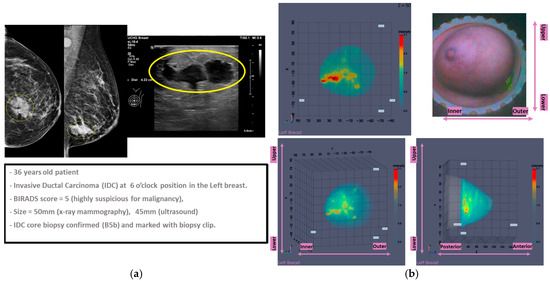

3.1. MWBI Partial Scan of Acceptable Quality and Relevance: Full Example of MWBI Patient Scan Imaging and Image Analysis Outputs for Radiological and Clinical Analysis